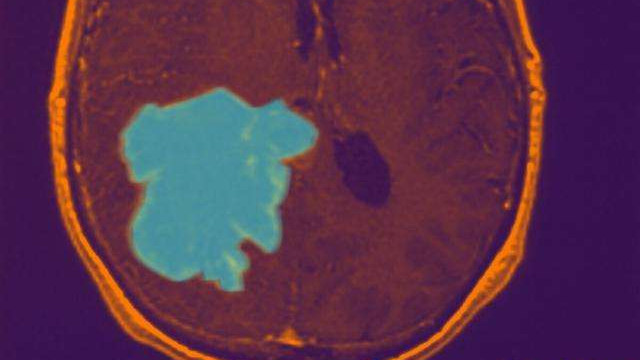

血管内肿瘤放疗“钇”步到位

钇[90Y]树脂微球是目前唯一获得国家药品监督管理局(NMPA)批准用于临床治疗的放射性微球 。 钇90树脂微球 , 就是树脂做的微球搭载放射性核素钇90 , 是钇90的载体 。 树脂有着良好的生物相容性 , 对组织无毒无害 。 钇90树脂微球是目前唯一的纯β射线治疗性核素微球 , 其选择性内放射治疗是一种应用治疗肝部肿瘤的方法 , 利用肝脏肿瘤独特的供血结构进行核素内放射治疗 。

“正常肝脏组织的血供约90%来自门静脉 , 而肝脏肿瘤约90%血供来自肝动脉 。 ”吕维富介绍 , 在党委书记、肝胆外科专家刘连新教授的关心指导下 , 医院引进该项先进的治疗技术 , 将钇90树脂微球通过局部精准介入手术直接注入肝脏肿瘤的供血动脉 , 在肝脏肿瘤处进行精准内放射治疗 , 从而达到强化抑制肿瘤的效果 , 延长患者生存时间 , “从治疗效果看 , 目前国外众多的使用患者大多数获得了满意的效果 。 ”

钇[90Y]玻璃微球融合了传统的放射治疗与经血管介入治疗 , 对目标肿瘤实施多重打击 , 该技术已被诸多国际指南推荐为肝癌的重要治疗手段 。